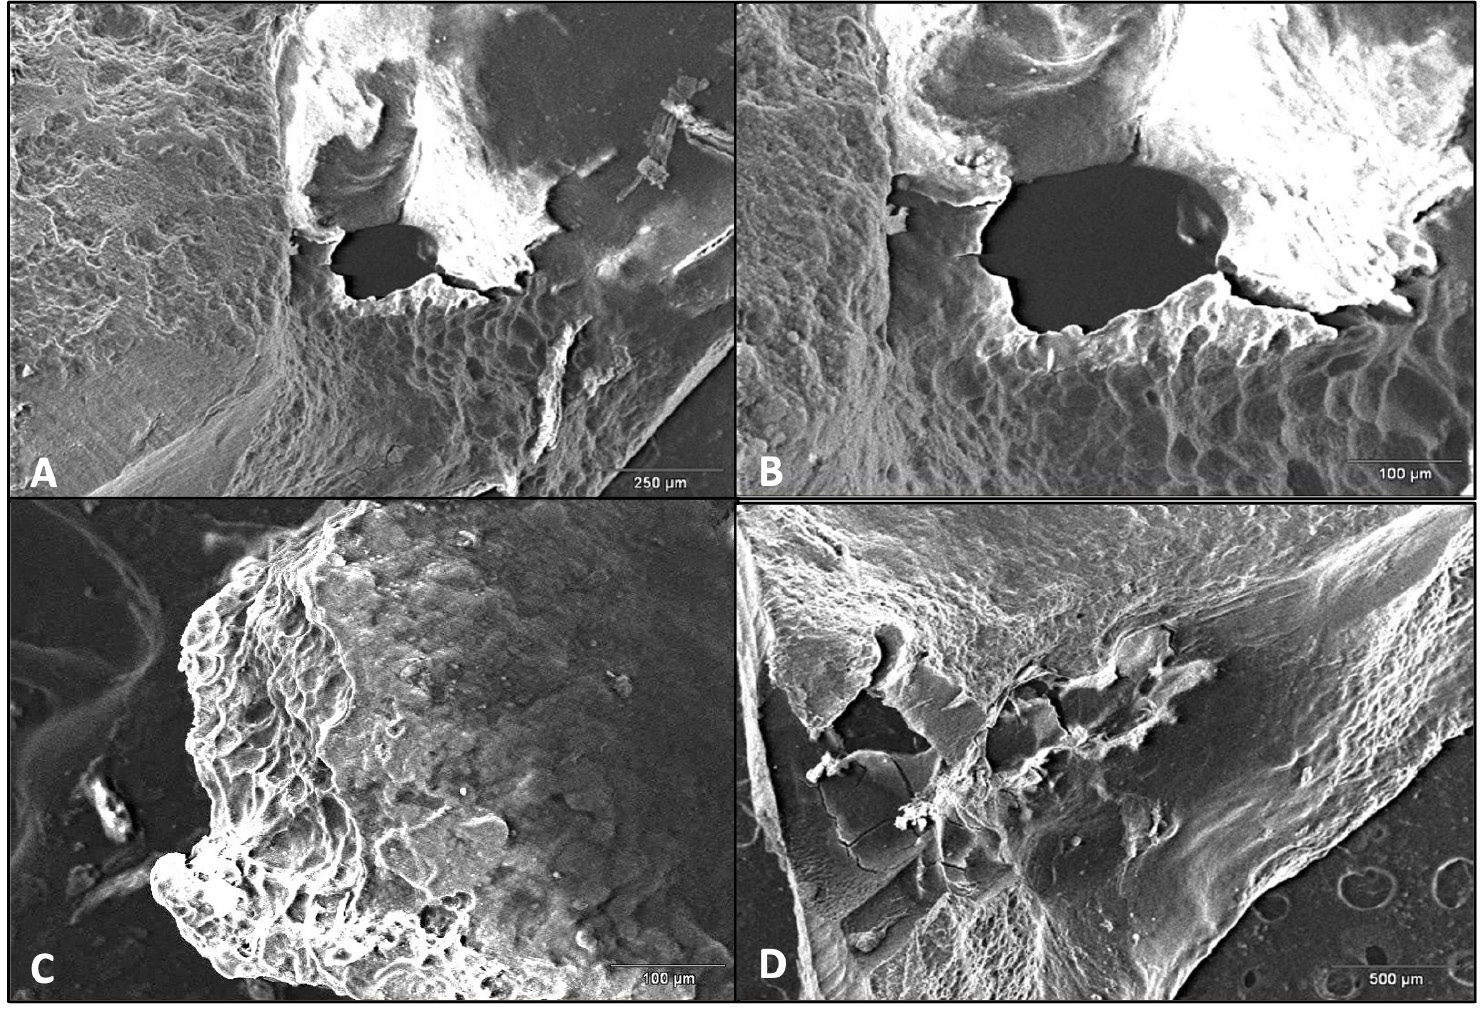

Resorption following infection may affect both the coronal and apical fragments. Additionally, involved root surfaces include the outer surfaces and it is not uncommon to for internal resorption to occur. Scanning electron microscopy (SEM) is an important technological aid for the analysis of the surface of the roots that are removed during endodontic surgery. Scanning electron microscopy enables the analysis of root morphology and the description of anatomy after resorption. The images presented in this review were captured with a SEM Hitachi Model S2460N (Hitachi, Tokyo, Japan) microscope with an acceleration voltage of 20 kV beam, and current of approx. 70 µA. The images present the SEM analysis of the surfaces of the fractured apical portion of #21 and the excised apical portion of #11. Interestingly, the area of the fracture of the apical fragment shows a geometric organization with vertical faults. As demonstrated earlier, fracture resistance is influenced by several factors, such as density, the diameter and the degree of obliteration depending on the patient’s age, presence of dentinal tubules and dentin microcomposition, which displays lower fracture resistance in deeper layers.28, 29

Figure 5 and Figure 6 show the root apexes of 2 excised fragments. On the root surface of tooth #21 (without root fracture), clear external resorption areas are visible even at lower magnification (×40); the same areas of resorption are less visible on the surface of tooth #11 at a higher magnification (×110). This indicates that the degree of external resorption was higher for #21 than #11.

The areas of resorption of tooth #11, that presented with the fracture of the third apical portion of the root, are more limited and shallower than those observed on the root surface of tooth #21, which has been completely avulsed, where the resorption was more aggressive and the lesions appeared to be diffuse, destroying the root surface (Figure 7, Figure 8).